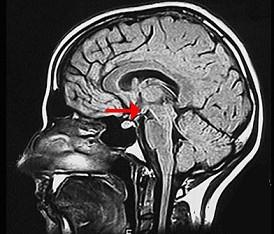

如图箭头所示为大脑哪个部位 ( )A、乳头体B、垂体C、后连合D、室间孔E、前连合

问题 如图箭头所示为大脑哪个部位 ( )

选项 A、乳头体 B、垂体 C、后连合 D、室间孔 E、前连合

答案 A